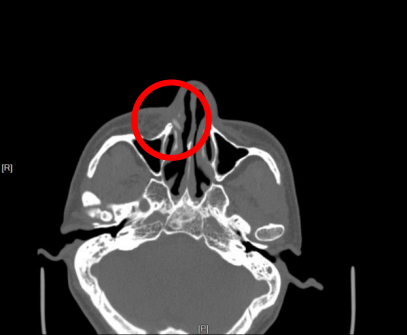

破案关键:把时间线往回翻到2018年 耳鼻咽喉科蒋锐主任接诊时,没有只盯着“现在流脓”,而是追问:有没有外伤史? 周先生的记忆被拉回到2018年,他曾因重物砸伤导致右侧颌面部损伤、上颌窦骨折,当时在上海当地医院做了一期清创缝合,但深部组织未进行充分探查。 蒋主任结合“糖尿病+外伤史+持续流脓+面颊瘘管”这组线索,判断:深部可能藏着问题。医院随即完善检查,并邀请上海外聘专家团队远程会诊。 ▲影像学(鼻窦CT、MRI)给出关键证据。 上颌窦/鼻腔区域出现不规则高密度影。结合外伤史,专家团队一致推断:骨折后遗留骨片长期滞留,在血糖控制不佳、免疫力下降的背景下持续刺激黏膜,诱发慢性感染,最终“打穿”形成面颊部瘘管。 一句话总结: 骨片没走,感染不走;血糖不稳,炎症更“恋战”~